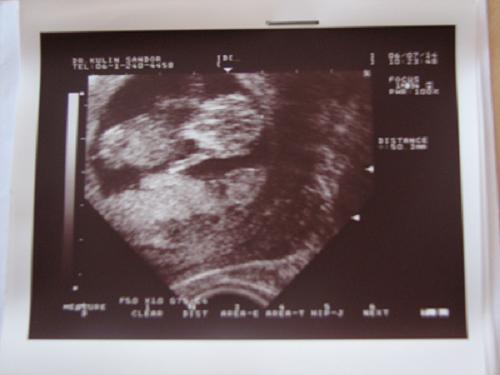

Pénteken elbúcsúztam Kulin dr-tól. A baba jól van, már 5 cm, és a tarkóredője is rendben van.(azért elmegyek egy genetikai vérvételre)

Remélem, itt nem zavar senkit az uh fotó. :lol:

Kép

Nyugodtan tegyél fel ilyen fotókat. Jól sikerült ez a felvétel. Nagyon cuki a két kis kezecskéje. Kár, hogy az arcocskáját nem mutatja. Majd legközelebb. Mindent nem lehet egyszerre. Ugye nem látom rosszul? Javíts ám ki nyugodtan!